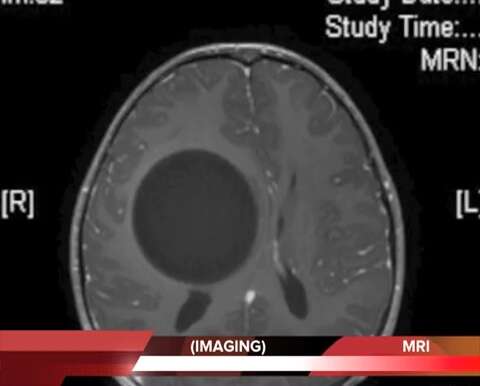

ראשו של הילד לפני הניתוח // צילום: בית החולים איכילוב

עוד הוסיפה קונסטנטיני: "כשהציסטה גדלה, פעולה שיכולה להמשך לפעמים שנים רבות, מופיעים תסמינים בהתאם למיקום בגוף והאיברים שהציסטה גורמת ללחץ עליהם. הילד שחלה פיתח במשך מספר חודשים חולשה מתקדמת בפלג הגוף השמאלי ואבחנה נעשתה באמצעות הדמיה של בדיקת MRI מוח שגילתה שמדובר בציסטה מוחית גדולה".